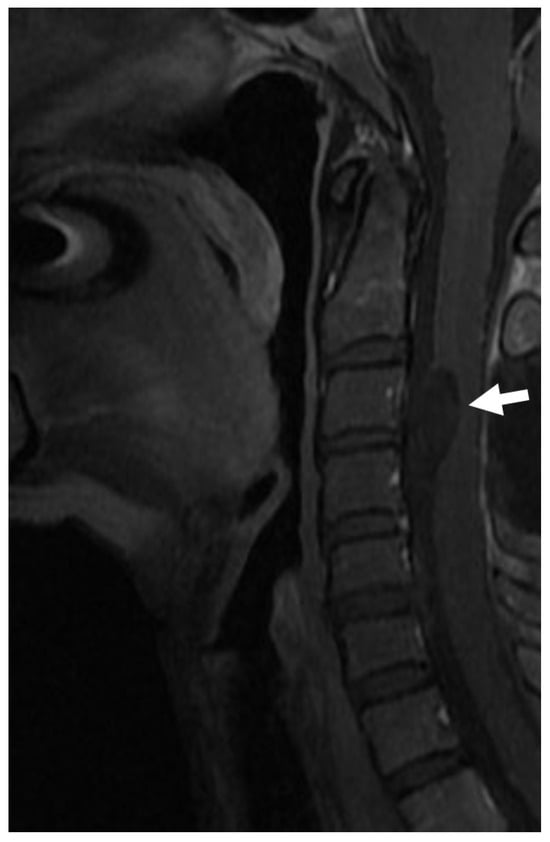

Figure 6. A neurenteric cyst located on the ventral side of the cervical spinal cord (white arrow). The patient presented in adulthood due to neurological symptoms related to the compression of the spinal cord.

Between days 18 and 20 of gestation, the yolk sac and amniotic cavity are temporarily connected by the neurenteric canal of Kovalevsky, which remains open for 3–4 days and closes with the closure of the primitive streak, leaving the notochord behind [5]. If this channel does not close, this leads to a permanent connection between the ectodermal (neural) and endodermal structures. This form of OSD is called a neurenteric cyst, which manifests as a tumour in the spinal canal (Figure 6). The cyst is surrounded by a characteristic enteric epithelium and can compress the spinal cord, leading to neurological deficits. A neurenteric cyst is always located on the ventral or lateral side of the spinal cord, never on the dorsal side. It is often associated with bony abnormalities of the spine and is never located under the S2 neurotome, as the nervous system distal to this level develops through a separate process called secondary neurulation. The neurenteric cyst occurred in only one case in our series: it became symptomatic in adulthood due to compression of the spinal cord and was not associated with a definite bony abnormality of the spine. A neurenteric cyst must be removed microsurgically. Any associated bony malformations or deformities of the spine should be treated separately, if necessary, with spondylodesis. In our series, one adult patient presented with a neurenteric cyst at the level of C2–3, which was successfully removed through a posterior approach.